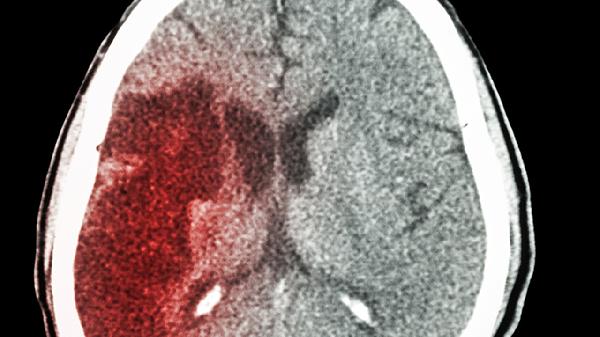

轻微脑梗伴随嘴角流口水可遵医嘱使用阿司匹林肠溶片、硫酸氢氯吡格雷片、阿托伐他汀钙片、胞磷胆碱钠片、尼莫地平片等药物。轻微脑梗可能与动脉粥样硬化、高血压等因素有关,需结合抗血小板聚集、调脂稳斑、改善脑循环等综合治疗。